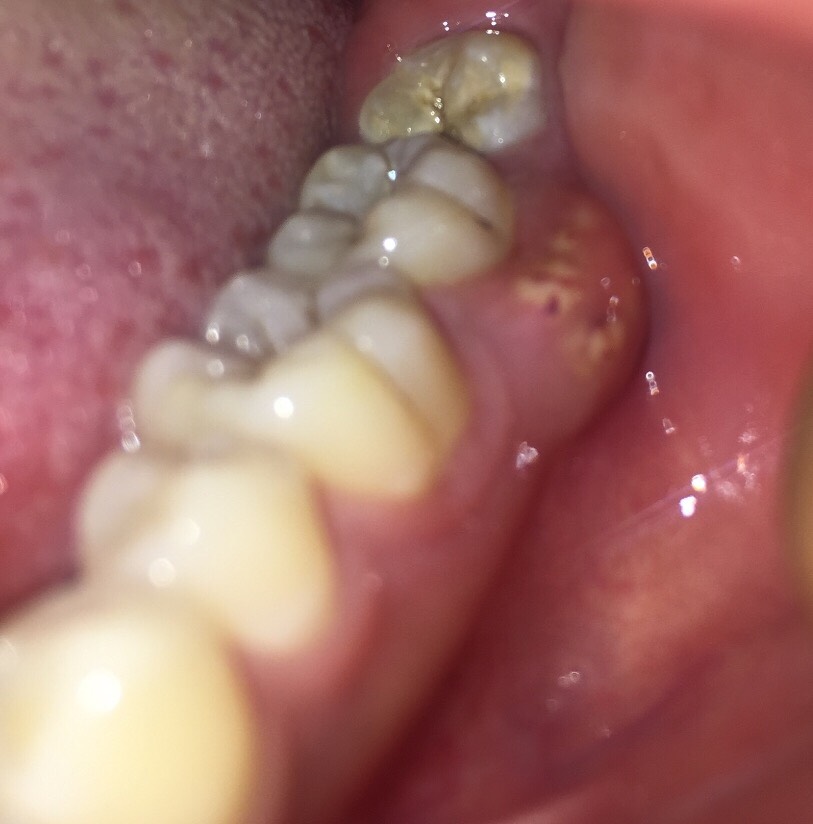

牙龈经常发炎红肿有脓包

牙龈肿有白色小脓包可能由根尖周炎牙周炎或牙龈炎引发,需根据病因采取针对性治疗根尖周炎后期可能形成根尖脓肿,表现为持续性跳痛,进食时疼痛加剧治疗需切开患处引流脓液,结合根管治疗术或牙髓血运重建术清除感染源疼痛剧烈时可服...